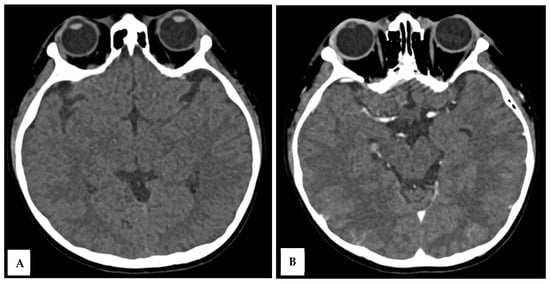

Over the next 48 h, the patient’s consciousness fluctuated, with a GCS deteriorating to E2M4V2. There were no significant changes in laboratory parameters. Brownish aspirate from the NGT prompted the discontinuation of dexamethasone. On day 5 of illness, a contrast-enhanced head CT scan was performed to evaluate for meningoencephalitis, which showed no abnormalities (Figure 1A,B).

Figure 1. A 10-year-old boy presented with visual disturbance and seizures. Axial non-contrast (A) and axial contrast-enhanced (B) head CT scans showed no evidence of meningoencephalitis, with findings within normal limits.

This case highlights that PRES is associated with reversible neurological complications in MIS-C. The temporal sequence, systemic inflammation, transient hypertension, seizures, and visual loss match the classic presentation of PRES [1,2]. MRI confirmed bilateral parieto-occipital and posterior temporal cortical–subcortical hyperintensities, consistent with vasogenic edema rather than cytotoxic injury. The normal CT findings emphasize the superior sensitivity of MRI in detecting PRES [5].

This case expands the limited literature linking PRES and MIS-C [4]. It also demonstrates that CT alone may fail to reveal early edema, underscoring the importance of MRI when neurological deterioration occurs in MIS-C patients [5].